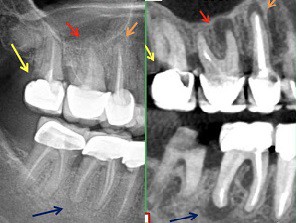

Miért nem elegendő a hagyományos panoráma röntgen?

A panoráma röntgenfelvétellel az állcsontok, fogak 2 dimenziós leképezését kapjuk meg, ahol az anatómiai képletek az egymásra vetülésük miatt megtévesztő képet mutathatnak. Az állcsont gerinc vastagságát, esetleges behúzódásokat nem lehet rajtuk látni, ezért biztonsággal kezelési tervet készíteni segítségükkel nem lehet. Ma panoráma röntgent egy kezdetleges kezelési terv elkészítéséhez szoktunk használni, aminek a segítségével a páciens megtudhatja jó eséllyel nagyságrendileg milyen kezelési összeggel kell számolnia az implantációs fogpótlásért.